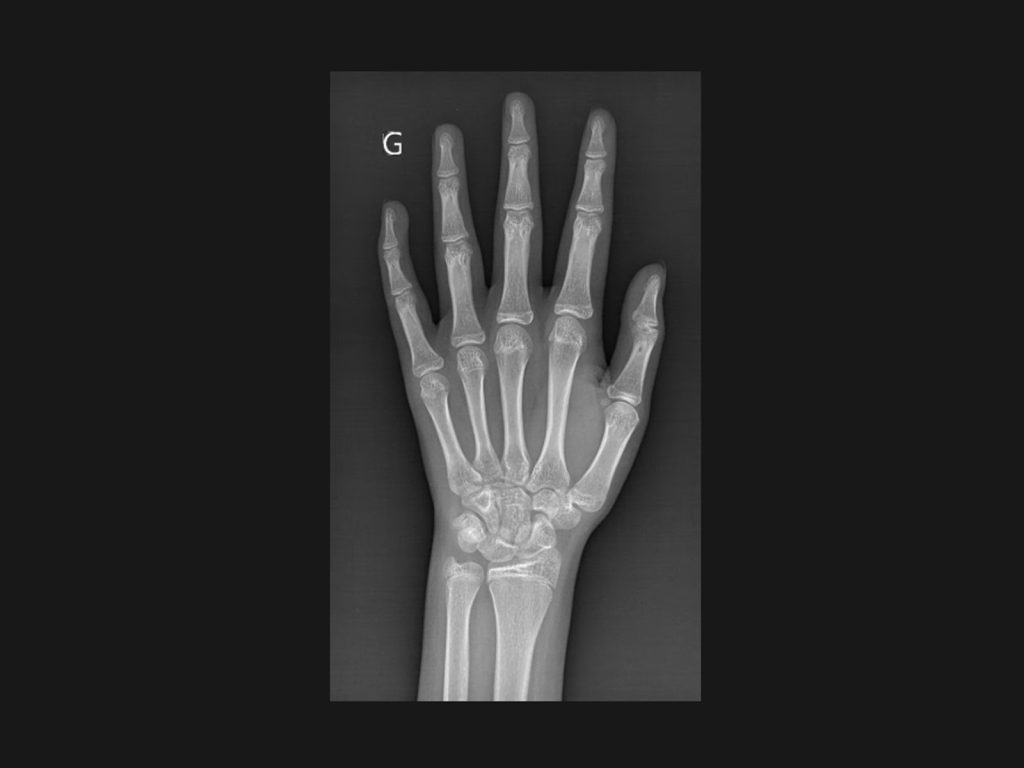

BoneAge este o solutie de inteligență artificială destinată evaluării vârstei osoase (bone age) pe radiografii pediatrice de mana, folosind metoda Greulich & Pyle Atlas

• Radiografia mâinii